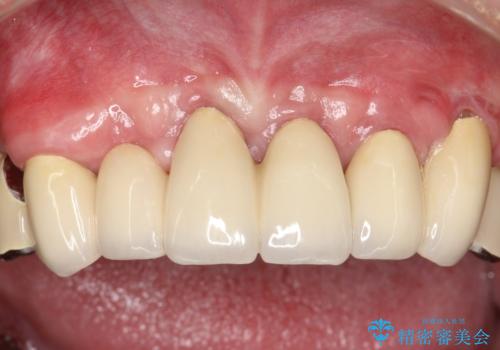

虫歯だらけ、歯周病 崩壊した口腔の再建 フルマウスリコンストラクション

費用・時間は多大にかかりましたが、今後しっかりと咬んで生活することができるでしょう。

かぶせ物の種類:PFZ / PFM metal occlusal